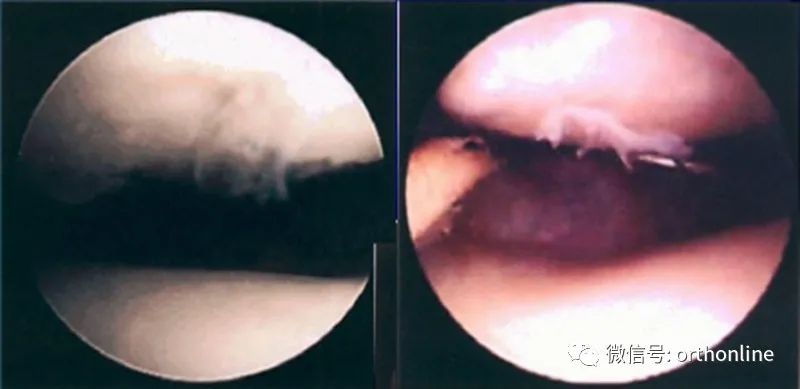

髌骨软化症Ⅰ级

髌骨软化症Ⅱ级